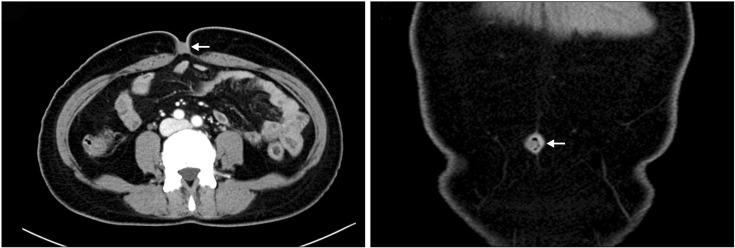

Endometriosis is a benign gynecologic disease that highly influences women of childbearing age. It is characterized by ectopic endometrial tissue. Primary umbilical endometriosis is a rare condition. It is a benign disease with endometrial tissue in an abnormal site in the navel. It may be accompanied with pain in the navel and a discolored bump. Among all locations with the potential for endometriosis, the navel has less than 1% incidence of primary umbilical endometriosis. In the present study, we reported a rare case of umbilical endometriosis revealed via a biopsy performed for a 49-year-old menopausal woman with the complaint of pain in the navel who underwent surgical excision and a biopsy after a scan.

子宫内膜异位症是一种对育龄女性影响极大的良性妇科疾病。其特征为异位的子宫内膜组织。原发性脐部子宫内膜异位症是一种罕见病症。它是一种良性疾病,在肚脐这个异常部位存在子宫内膜组织。可能伴有肚脐疼痛和变色肿块。在所有可能发生子宫内膜异位症的部位中,原发性脐部子宫内膜异位症的发病率低于1%。在本研究中,我们报告了一例罕见的脐部子宫内膜异位症病例,该病例是通过对一名49岁绝经女性进行活检发现的,该女性因肚脐疼痛前来就诊,在扫描后接受了手术切除及活检。